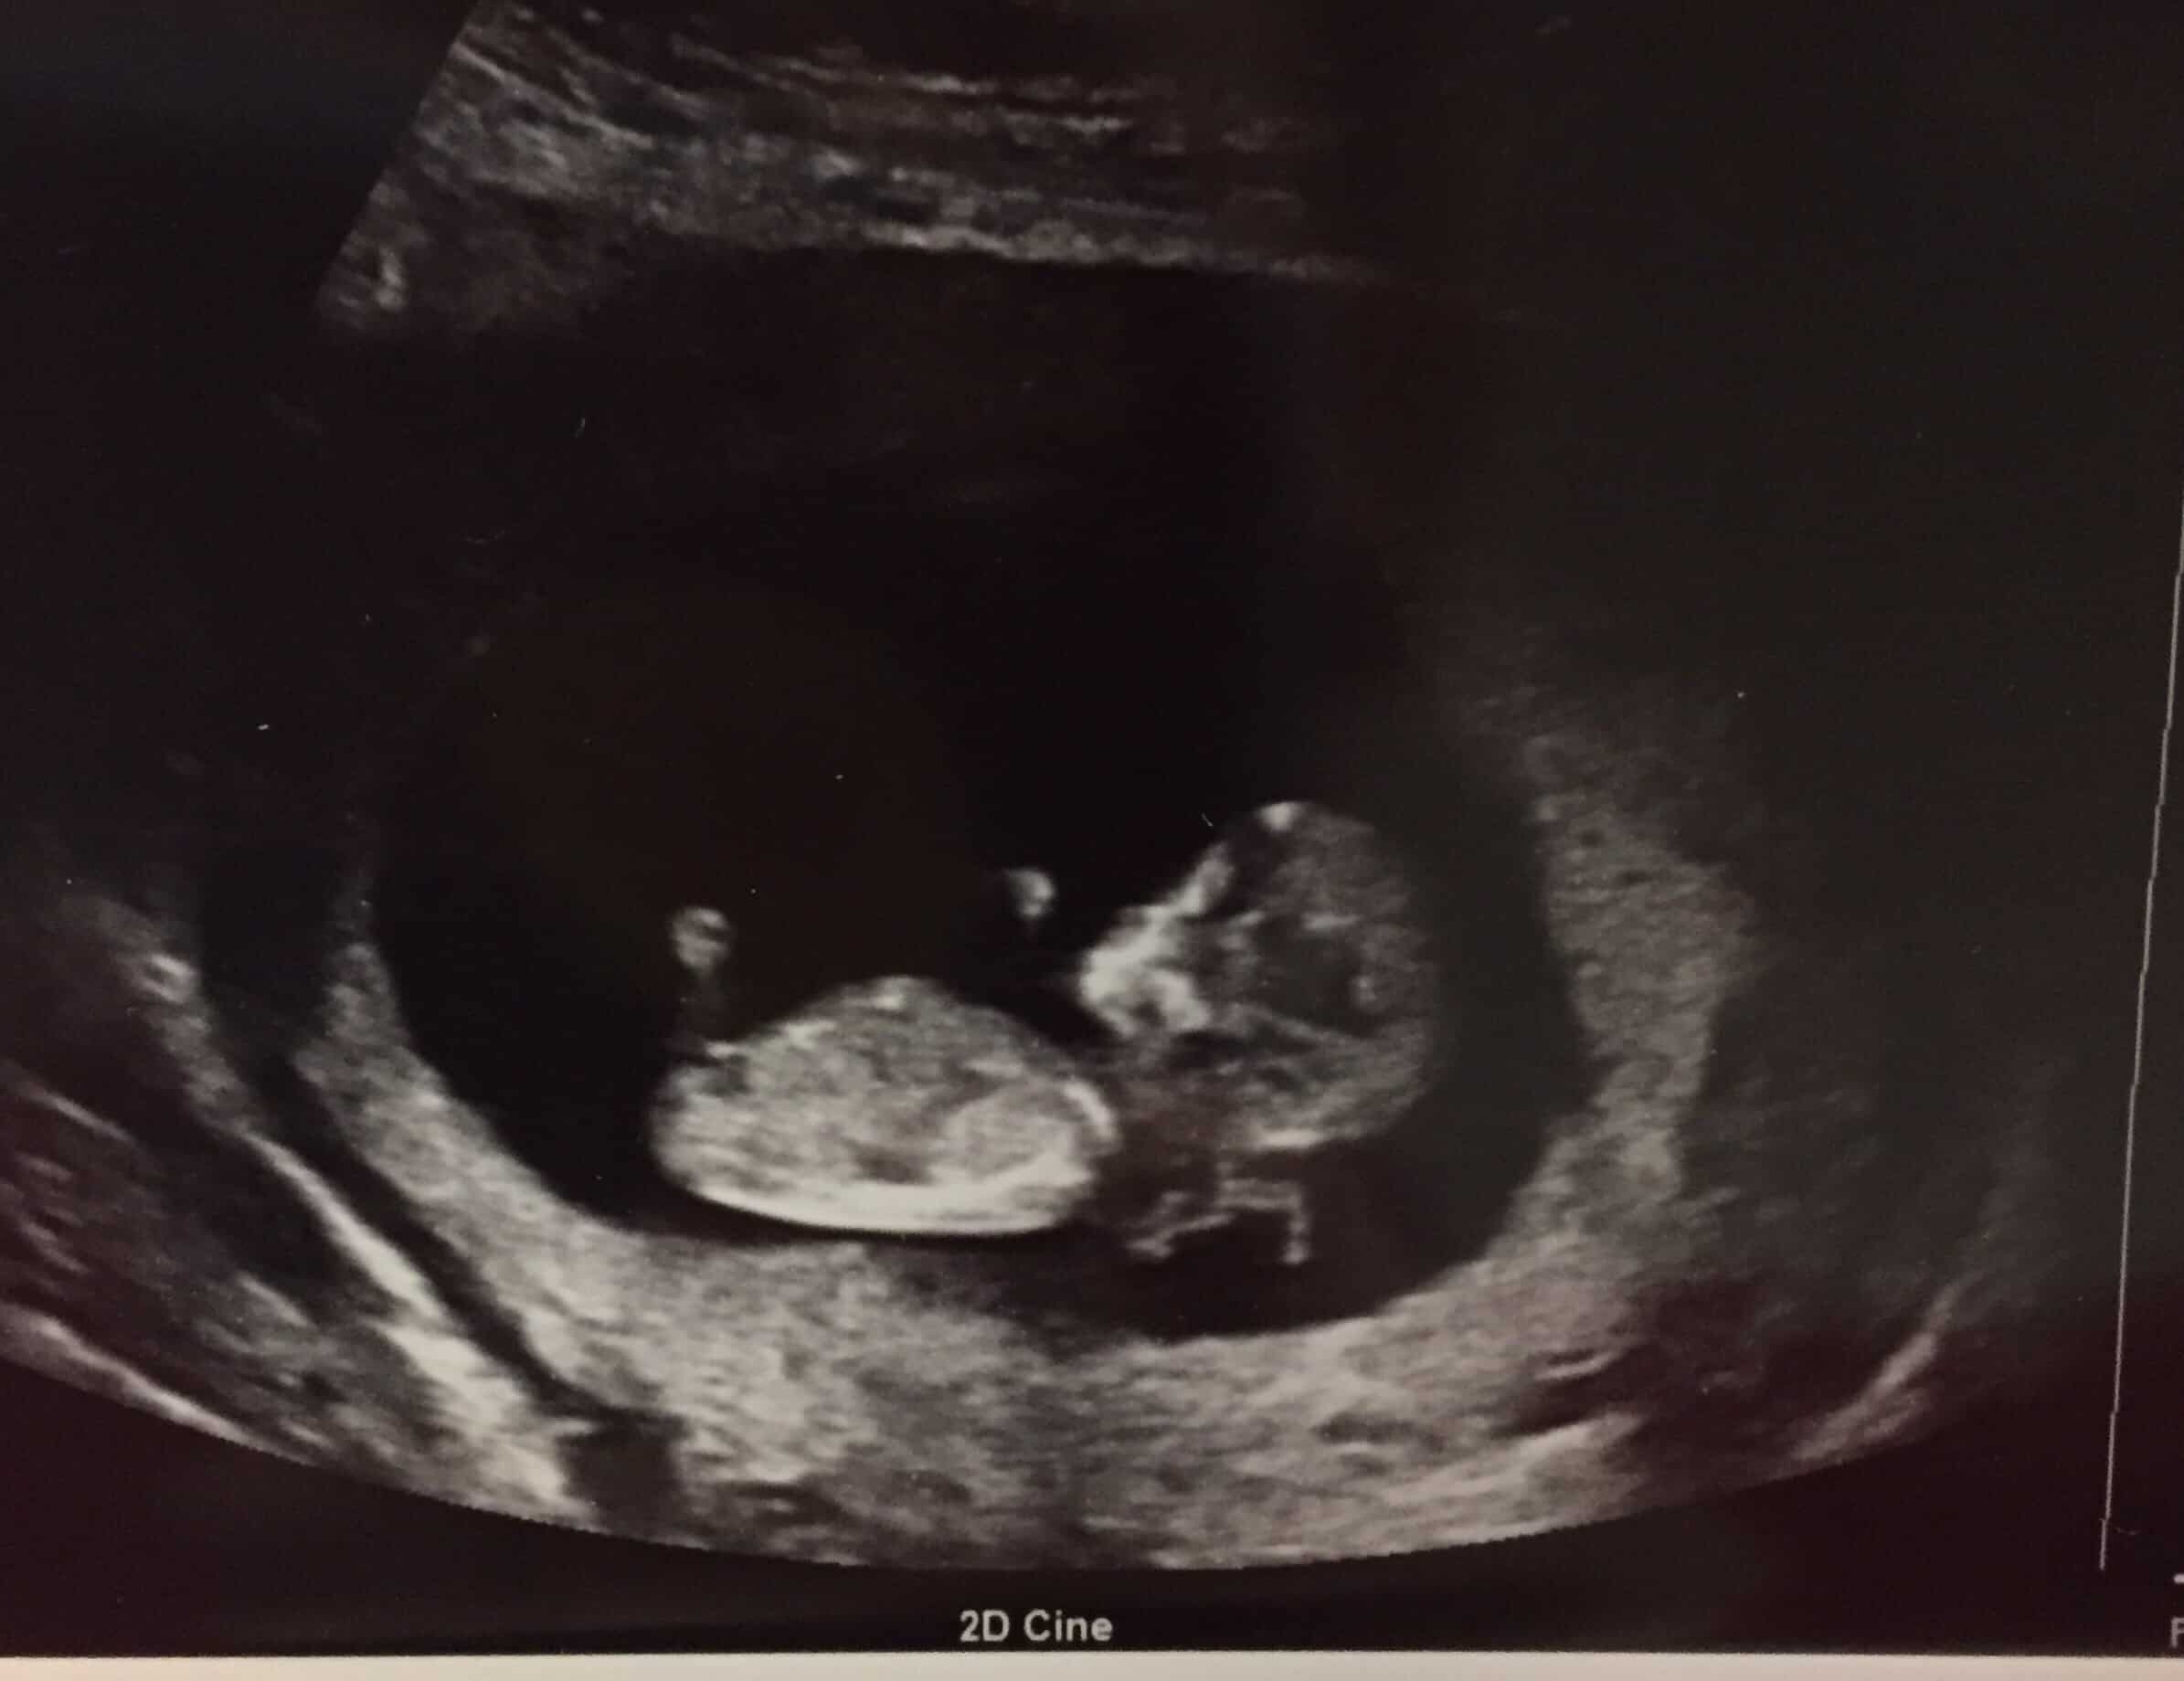

Clinical Considerations in the Third Trimester . Gestational age assessment by ultrasonography in the third trimester (28 0/7 weeks of gestation and beyond) is the least reliable method, with an accuracy of Β± 21-30 days 19 20 24 . Because of the risk of redating a small fetus that may be growth restricted, management decisions based on third-trimester ultrasonography alone are especially problematic; therefore, decisions need to be guided by careful consideration of the entire clinical . . .

When the assignment of gestational age is based on a third-trimester ultrasound , it is difficult to confirm an accurate due date . Follow-up of interval growth is suggested 2 to 3 weeks following the ultrasound .

As pregnancy progresses, the accuracy of an ultrasound for predicting due dates decreases . Between 18 and 28 weeks of gestation, the margin of error increases to plus or minus two weeks . After 28 weeks, the ultrasound may be off by three weeks or more in predicting a due date .